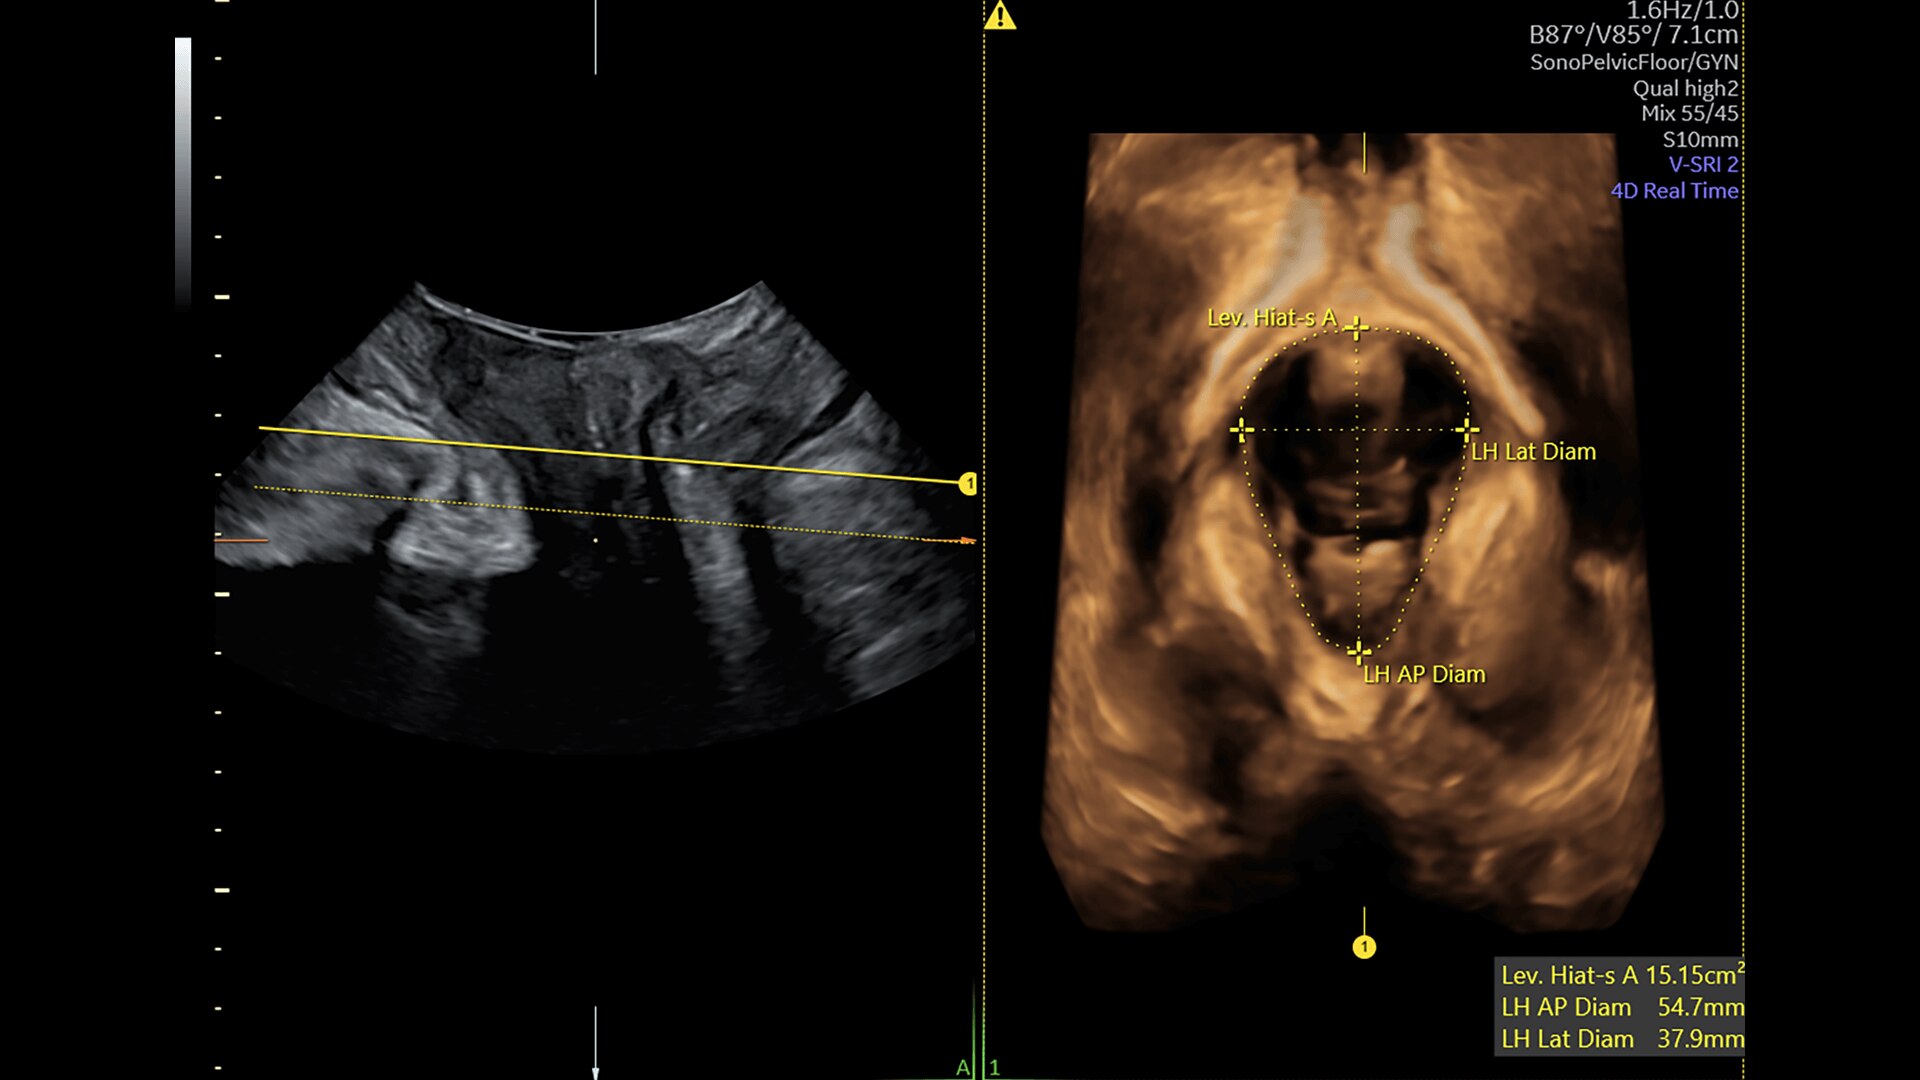

Pelvic Health

Offer patient answers faster with Ai-based automation tools